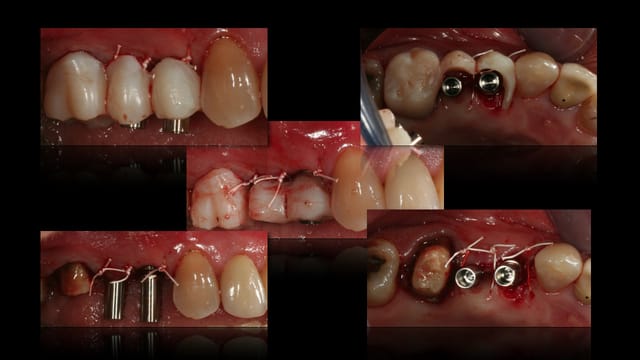

puisqu'il se passe pas grand chose en ce moment sur eugenol, voici un cas de ce matin.

- transformation du bridge pro en guide chir

- extraction 24

- mise en place d'implant en 24 et 25 : astra 4*13 et 4*8, comblement du gap au Bio-oss

- transformation du guide chir en bridge provisoire sur implant ( sur pilier uni )